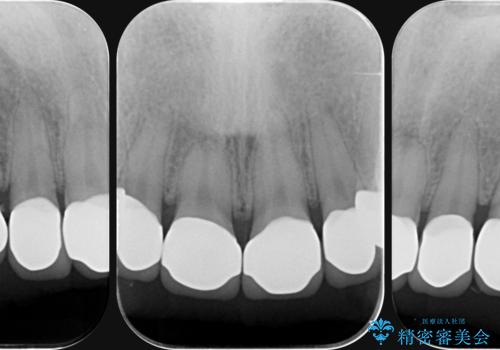

充填部位が大きく、再度充填をするには神経と近くなり抜髄のリスクが高まるため、劣化の少ないセラミックでフルカバーするセラミッククラウン治療を行うこととしました。

- 79.2万円(ジルコニアクラウン×6・仮歯×6)費用は治療当時の料金となります

前歯の小さな虫歯は、除去したのちコンポジットレジンと言われる樹脂を充填する処置を行うことが多々あります。

しかし、経年劣化が早く着色や小さな虫歯が再発しやすいため、ある程度の大きさになってしまった場合セラミッククラウンで置き替えた方が神経を温存し長期的な予後の期待できる治療となります。